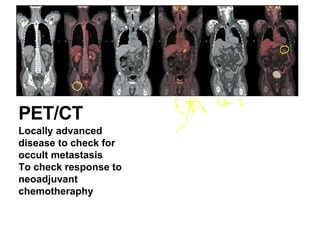

PET/CT

Locally advanced

disease to check for

occult metastasis

To check response to

neoadjuvant

chemotheraphy